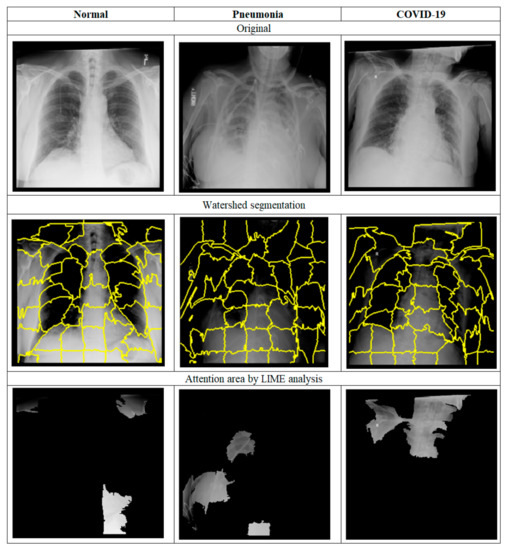

3. Materials and Methods

3.2. Methods